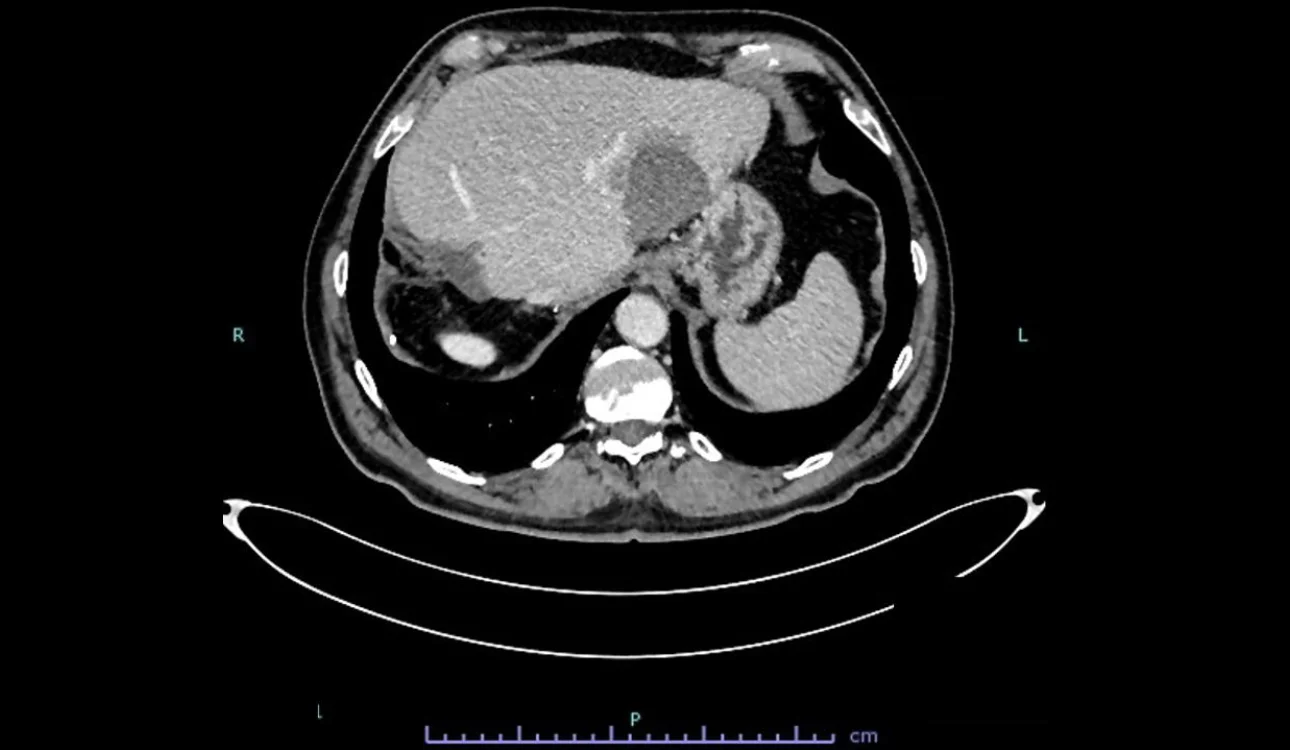

After a month, a CEUS exam was performed to assess the post-thermal ablation zone. The post-thermal ablation zone in the arterial phase after injection of 1.2 ml of Sonovue intravenously (Fig 2). A clear margin of necrosis developed from post-thermal ablation was visible. The necrotic region didn’t undergo contrast enhancement in any phase of the examination. In the portal phase (Fig 3-4), contrast washout was observed in the liver parenchyma adjacent to the ablation zone (arrows). Then a CT scan was performed to verify the case (Fig 5). A hepatic vein adjacent to the post-thermal ablation recurrence area was visible.

thermal-ablation-fig5-pc

Fig. 5 Venous phase of CT image. A hepatic vein adjacent to the post-thermal ablation recurrence area was visible.